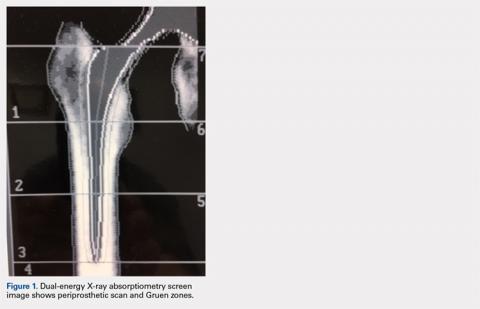

It is possible to monitor changes in BMD around implants using the periprosthetic software application (this usually needs to be purchased separately from standard software that is installed with a system set-up). Dramatic loss of bone due to stress shielding after total hip arthroplasty (THA) can be a risk factor for implant migration or potentially outright failure of fixation or breakthrough. If bone loss occurs and is observed in the early stages, then antiresorptive treatment can be initiated to limit further loss.18,19 (Figure 1) shows the image from a periprosthetic scan.

Standard Gruen zones are the default ROIs.20 It is well established that BMD loss differs from zone to zone, with the greatest loss in zone 7 after THA.